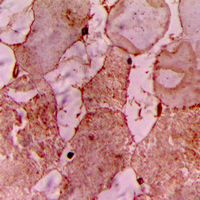

IHC (Immunohiostchemistry)

(Immunohistochemical analysis of CARK staining in human heart formalin fixed paraffin embedded tissue section. The section was pre-treated using heat mediated antigen retrieval with sodium citrate buffer (pH 6.0). The section was then incubated with the antibody at room temperature and detected using an HRP conjugated compact polymer system. DAB was used as the chromogen. The section was then counterstained with haematoxylin and mounted with DPX.)